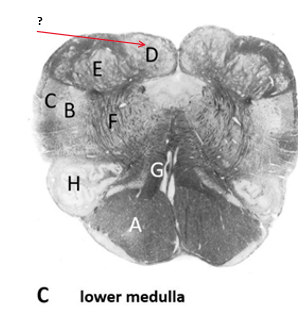

Name this, state its function and pathway[5 marks].

Pyramid.

Name this and state its function.

Nucleus Gracilis.

Name this , state its function, pathway and tract its involved to.

Nucleus cuneatus.

Cuneatus receptors–>Dorsal roots–>nucleus cuneatus–>Thalamus–>somatosensory cortex.

Inferior olivary nucleus:

Medial lemniscus.

Name this, state its functions within their tracts, different tracts and regulators of the their tracts.

Reticular formation.

Ascending tracts:

Descending tracts:

Name this.

Spinal Trigeminal nucleus.

Spinal trigeminal tract.

Questions:

Descending pathway:

Ascending pathways: